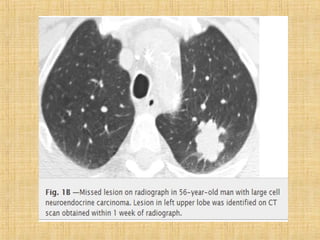

As principais informações do documento são: 1. Discute os padrões de doença pulmonar causados por metástases, incluindo nódulos, espessamento intersticial e obstrução das vias aéreas. 2. A prevalência de metástases pulmonares varia de 30-55% dependendo do tumor primário, e são mais comuns em pacientes acima de 50 anos. 3. Os achados clínicos mais comuns são dispneia, hemoptise e febre, enquanto exames de escarro ou lavado brô